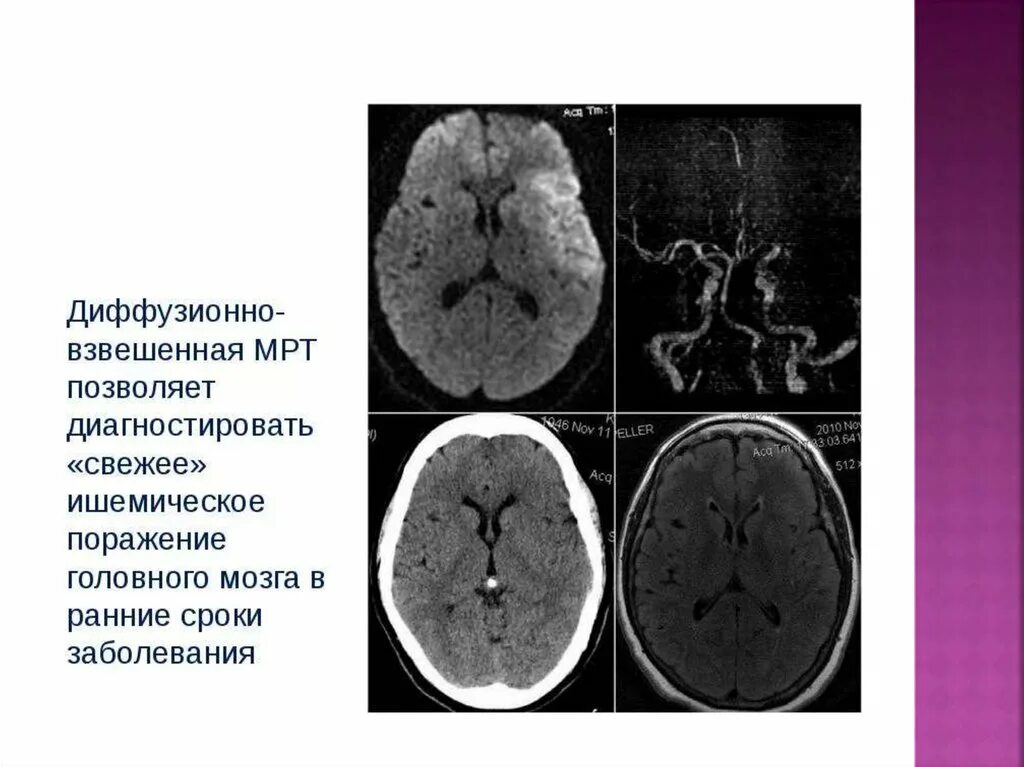

Диффузные изменения головного мозга